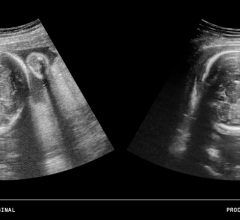

Researchers at the University of North Carolina at Chapel Hill have achieved higher resolution ultrasounds that can help detect tumors. They combined ultrasound with a contrast agent comprised of micro-sized bubbles that pair with an antibody produced at elevated levels by many cancers. By binding to the protein SFRP2, the microbubble contrast agent greatly improves the resolution and tumor-detecting ability of scans produced by ultrasound.